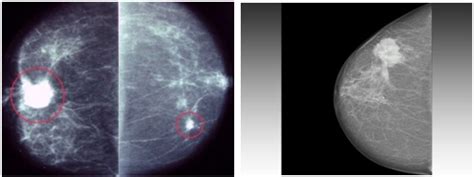

Alright guys, let’s get straight to it: what does a 4cm breast cancer mass actually mean? When we talk about cancer, size is one of the first things doctors look at. Think of it like this: a bigger mass often means the cancer has had more time to grow and potentially spread. A 4 cm mass, for reference, is roughly the size of a large grape or a small plum. Now, in the world of breast cancer staging, this size is significant. It typically falls into Stage II breast cancer, but this can vary depending on whether the cancer has spread to lymph nodes or other parts of the body. Stage II breast cancer means the tumor is larger than 2 cm but not more than 5 cm, and it hasn’t spread to distant parts of the body, or it has spread to a few nearby lymph nodes. If a 4 cm mass is found, doctors will immediately be looking to see if it has invaded the lymph nodes under the arm. The presence or absence of cancer cells in these nodes is a critical factor in determining the overall stage and the best course of treatment. It’s not just about the number ‘4 cm’; it’s about what that number represents in terms of the cancer’s characteristics and its potential behavior. Doctors use imaging techniques like mammograms, ultrasounds, and MRIs to measure the size of the tumor, and often, a biopsy is performed to confirm the diagnosis and gather more information about the type of cancer cells present. This detailed information is absolutely vital for crafting a personalized treatment plan. So, while a 4 cm mass is a serious finding, it’s just one piece of the puzzle. The type of cancer cells, their grade (how abnormal they look), and whether they are hormone receptor-positive or HER2-positive also play enormous roles in how the cancer will be treated and what the outlook might be. We’ll delve deeper into these aspects, but for now, the key takeaway is that a 4 cm mass indicates a tumor of considerable size that requires thorough evaluation.

Let’s wrap this up by stressing something absolutely vital: the importance of early detection in breast cancer . When we talk about a 4 cm mass, it’s a finding that highlights why catching things sooner is always better. Early detection means finding breast cancer at its earliest, most treatable stages, often before symptoms even appear. Think about it: if a tumor is smaller, say 1 cm or even less, it’s much more likely to be contained within the breast and hasn’t had a chance to spread to the lymph nodes or other parts of the body. This translates to simpler treatments, often less aggressive ones, and a significantly higher chance of a full recovery with a better prognosis. Methods like mammograms are our superheroes here. Regular mammograms are the gold standard for screening, allowing doctors to spot tiny abnormalities that are invisible to the naked eye and undetectable by touch. For women over 40, or those with a higher risk, annual mammograms are typically recommended. Clinical breast exams by a healthcare professional and breast self-awareness – knowing what’s normal for your breasts and reporting any changes promptly – are also crucial components of early detection. If a mass is found when it’s small, the treatment might involve just a lumpectomy with radiation, avoiding the need for a mastectomy and extensive chemotherapy. This significantly impacts quality of life during and after treatment. While we’ve discussed a 4 cm mass, which is larger, the principles of early detection mean we aim to find cancers before they reach that size. So, the message is clear, guys: don’t skip your screenings. Be proactive about your breast health. If you notice any changes – a lump, skin dimpling, nipple discharge, or pain – don’t wait. See your doctor right away. The earlier breast cancer is found, the more treatment options are available, and the better the outcomes. Early detection truly saves lives, giving you the best possible chance against breast cancer, no matter its size when found.